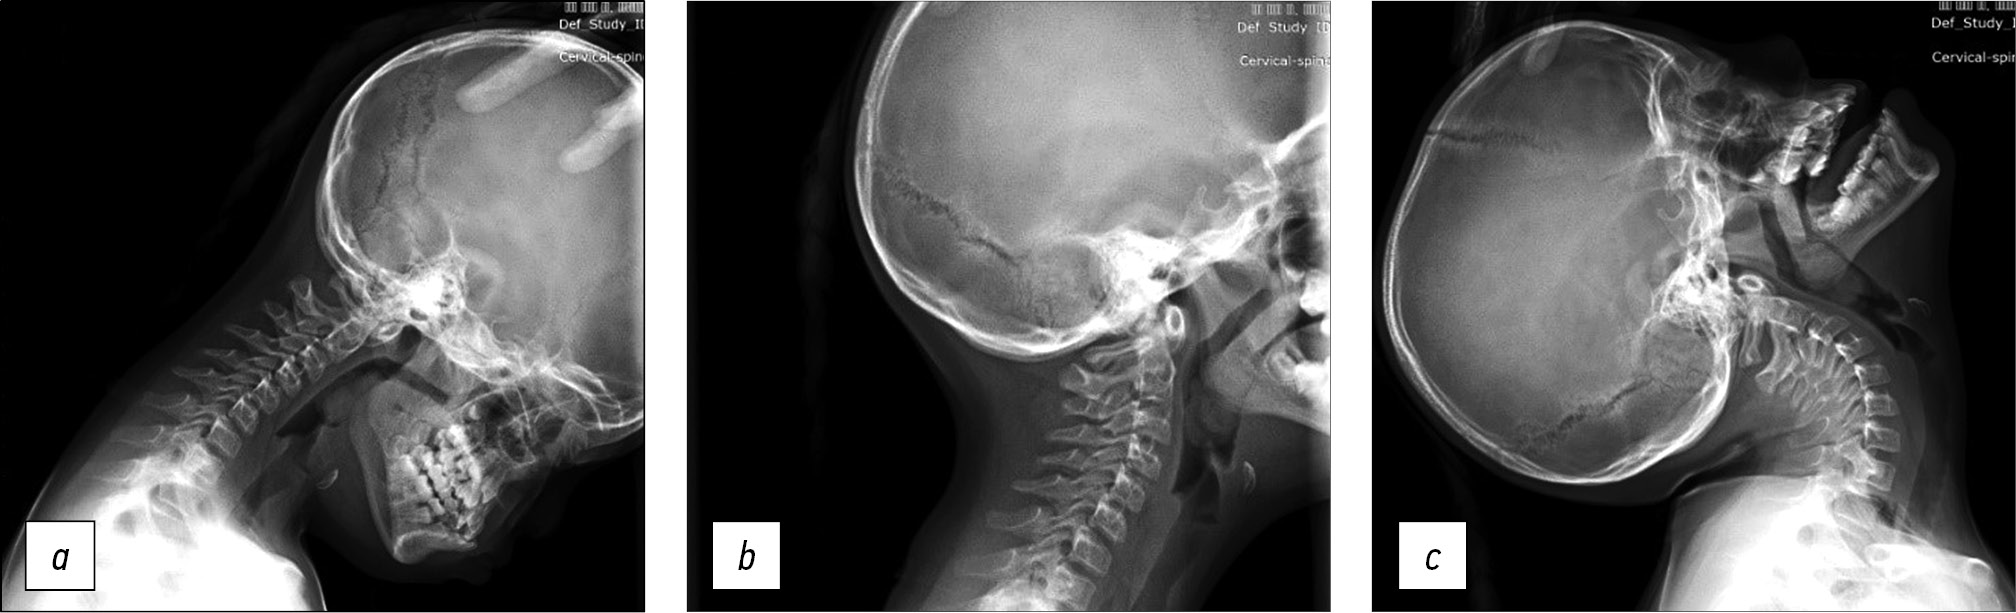

In the absence of signs of neurologic deficit, functional radiographs of the cervical spine were obtained in lateral projection in maximum flexion, extension, and neutral positions. This method of radial diagnosis allows us to fully assess the presence of instability in the craniovertebral junction and indirectly judge the magnitude of spinal canal stenosis and developmental anomalies of the cervical spine [8, 9] (Fig. 1).

Fig. 1. Functional radiography of the cervical spine in lateral projection: a — in flexion position, b — in neutral position, c — in extension position.